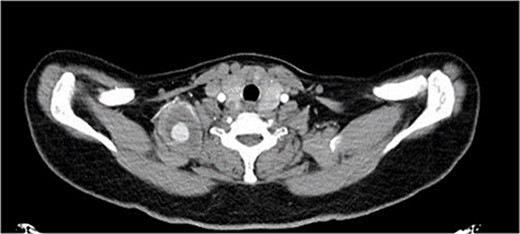

The patient underwent open repair of the pseudoaneurysm. Procedure details: a 2 cm supraclavicular transverse incision was made, the subplatysmal flap was raised and the underlying fat pad was dissected, exposing the scalenus anterior muscle. Pseudoaneurysm was found on the transverse cervical branch of the subclavian, imbedded within the scalenus medius muscle. C-5, C-6, and the long thoracic nerves were identified (Fig. 2). Pseudoaneurysm was mobilized, inflow was controlled by 2–0 silk stitch and clips. The pseudoaneurysm was resected completely (Figs 3 and 4). The patient tolerated the procedure and was discharged without reported complications.

The supraclavicular incision and well-capsulated pseudoaneurysm with scalene muscle fully dissected intraoperatively.